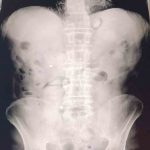

Şüphelilerin hastanede yaptırılan kontrolleri ve çekilen röntgen filmleri sonucunda mide ve bağırsaklarında çok sayıda uyuşturucu madde içeren kapsül bulunduğu tespit edildi. Hastanede kontrollü şekilde gözetim altında tutulan şüphelilerden tıbbi müdahaleler neticesinde toplam 93 parça halinde 1 kilo 70 gram metamfetamin ele geçirildi.